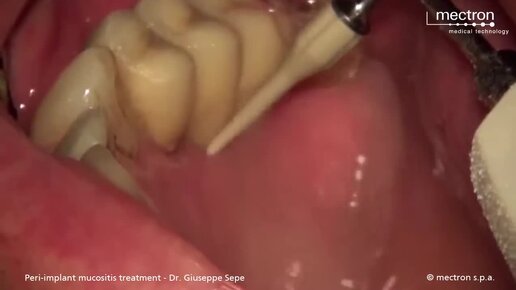

Лечение периимплантитного мукозита